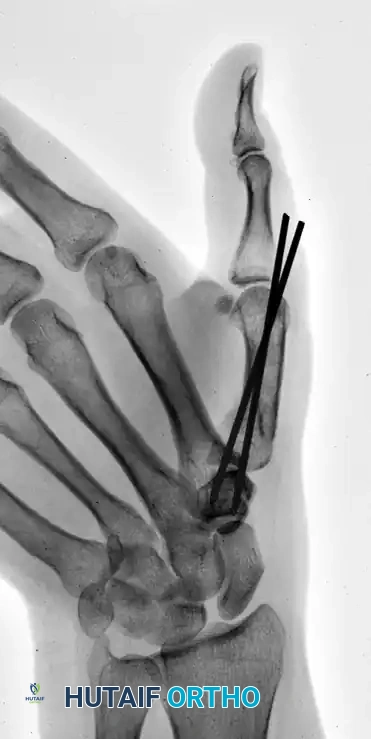

This comprehensive guide details the advanced principles of closed pinning, with a specific focus on the Wagner technique for first carpometacarpal (CMC) joint fracture-dislocations (Bennett fractures), extra-articular metacarpal base fractures, and complex phalangeal reconstructions.

The Wagner Technique for Closed Pinning

The Wagner technique is the gold standard for the closed management of Bennett fractures. It relies on reversing the deforming forces through specific manual maneuvers, followed by percutaneous transarticular fixation.

Step 3: Percutaneous Pin Placement

While an assistant (or the surgeon's non-dominant hand) maintains the reduction, the pinning is executed:

* Drill a 0.045-inch or 0.062-inch Kirschner wire into the base of the metacarpal.

* Direct the wire proximally across the CMC joint and into the body of the trapezium.

Surgical Warning: Fixation merely to the volar oblique fragment is often insufficient to prevent the loss of fracture reduction. The K-wire must engage the trapezium to neutralize the deforming forces of the APL.

Sometimes, more than one Kirschner wire is required to achieve absolute rotational stability. Depending on the fracture geometry, the secondary wire may engage carpal bones other than the trapezium (such as the trapezoid or the capitate) for adequate fixation.

The following sequence illustrates the progression from injury to successful closed reduction and K-wire fixation into the trapezium: